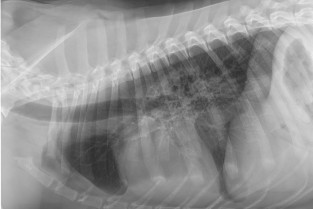

Le thème retenu cette année est le THORAX : imagerie, chirurgie, pneumologie et cardiologie se côtoieront sur des sujets ciblés. Des travaux dirigés de lecture de radiographies thoraciques, gestes chirurgicaux, cas cliniques, ainsi que des travaux pratiques d’échocardiographie illustreront les exposés.